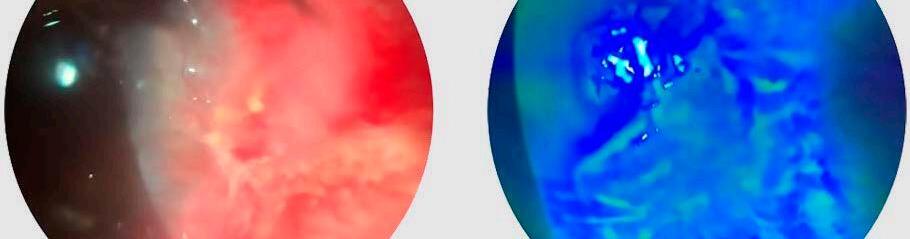

Presentamos el caso de una paciente femenina de 74 años, que concurre a la Guardia por dolor ocular en su ojo izquierdo de tres días de evolución. Al examen físico presenta agudeza visual mejor corregida de 20/30 en ojo derecho, 20/40 en ojo izquierdo. A la biomicroscopía del ojo izquierdo observamos una úlcera corneal que tiñe con fluoresceína en forma de semiluna, ubicada inferonasal perilimbar desde hora 9 hasta hora 5, infiltrada, con adelgazamiento sectorial (Imagen A y B). En el ojo derecho se observa pannus inferonasal, sin tinción.

Obtuvimos una buena respuesta al tratamiento tópico y sistémico, observando al tercer dia una úlcera de menor tamaño (Imagen C y D), y se evidenció cierre completo de ésta luego de cinco días de tratamiento (Imagen E y F), por lo que cual se realizó un tapering de la meprednisona vía oral, manteniendo tratamiento tópico con colirios fortificados hasta la obtención del resultado de la muestra, la cual arrojó resultados negativos para bacterias, hongos y parásitos universales.

Imagen A : Córnea sin tinción. Úlcera inferonasal perilimbar infiltrada.

Imagen C : Lesión corneal 72 hs después de iniciado el tratamiento tópico y vía oral. Observamos la pupila dilatada bajo el efecto de la atropina tópica, y una reducción del tamaño de la úlcera.

Imagen E : Cierre completo de la lesión.

Imagen B : Observamos la tinción de dicha lesión corneal con fluoresceína.

Imagen D : Observamos la tinción de dicha lesión corneal con fluoresceína.

Imagen F : Lesión con tinción con fluoresceína.